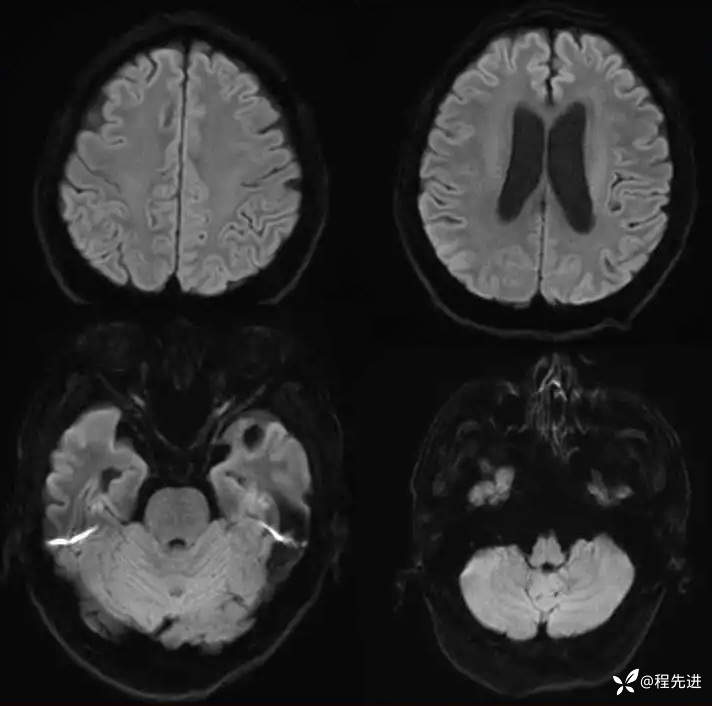

患者性别:男

患者年龄:64岁

主诉:全身乏力,手脚发麻半日。

现病史:患者确诊肺腺癌1年余,化疗联合靶向治疗,门诊转来。

癌胚抗原:14.67 ng/mL

MR平扫+增强: